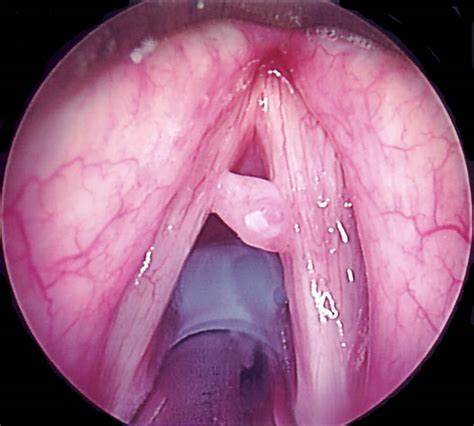

Kyste Corde Vocale / Vocal Cord Lesions - Stanford Children's Health - Les nodules des cordes vocales sont des gonflements bénins de la taille d'une tête d'épingle parfois, il s'agit d'une cavité remplie de liquide (kyste).. The size of vocal cords affects the pitch of voice. In microlaringoscopia si evidenzia una neoformazione cistica di contenuto mucoso che viene asportata con l'ausilio di micropinza e microforbice. Vue laryngoscopique des cordes vocales … wikipédia en français. Depuis un an je fais de la rééducation pour un probleme de kyste sur les cordes vocales. In humans, vocal cords, also known as vocal folds or voice reeds are folds of tissue in the throat that are key in creating sounds through vocalization.

Les nodules des cordes vocales sont des gonflements bénins de la taille d'une tête d'épingle parfois, il s'agit d'une cavité remplie de liquide (kyste).

In microlaringoscopia si evidenzia una neoformazione cistica di contenuto mucoso che viene asportata con l'ausilio di micropinza e microforbice. Il a également décliné tous ses engagements jusqu'à la fin 2009, ses médecins ayant diagnostiqué un kyste sur l'une de ses cordes vocales qui nécessite une intervention chirurgicale. Vue laryngoscopique des cordes vocales … wikipédia en français. S'utilise avec les articles la, l' (devant une voyelle ou un h. Ce trouble porte sur une ou plusieurs.

Vocale anatomie exprimer voix énoncer larynx gorge goulot kyste désordre trouble laryngien laryngique laryngé laryngoscopy polype respiratoire système anatomique biologie expirer inspirer respire respirer.